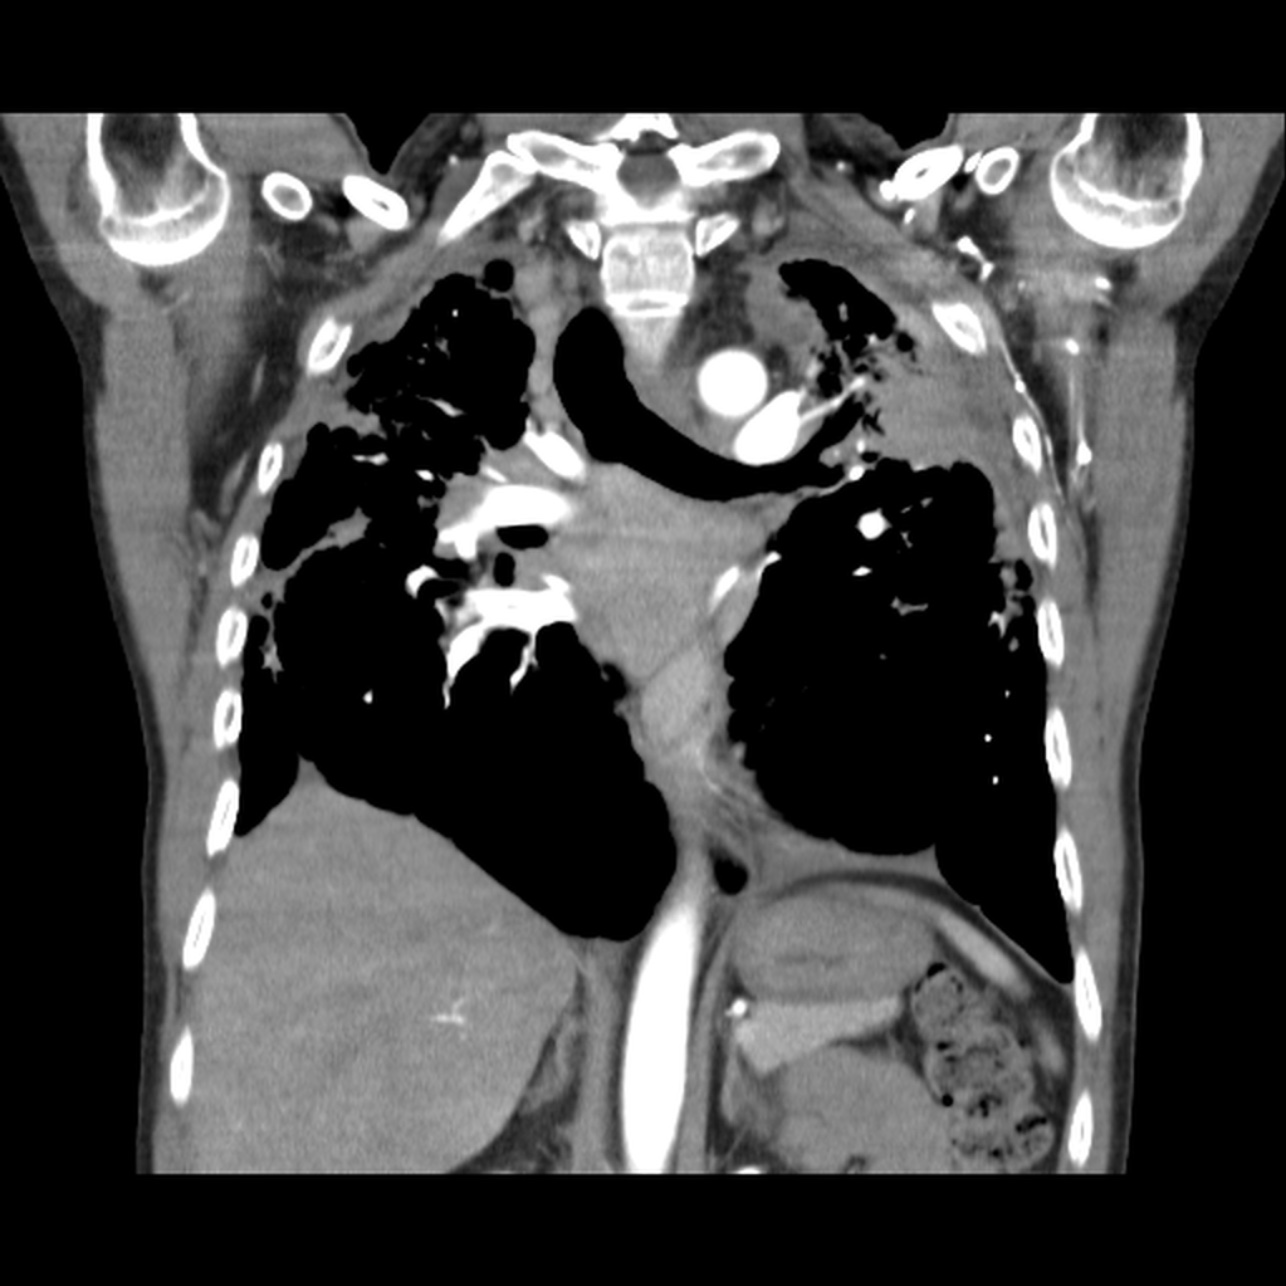

Hombre de 61 años asintomático. Colonoscopia demuestra válvula ileocecal ulcerada y estenótica. No hay antecedente de Enfermedad Inflamatoria Intestinal.

Con base en lo anterior el siguiente paso a seguir es?

a) Valoración por cirugía general.

b) Iniciar tratamiento con anti-inflamatorios e inmunosupresores.

c) Biopsia bajo guía ecográfica de las lesiones focales hepáticas.

d) Repetir colonoscopia.